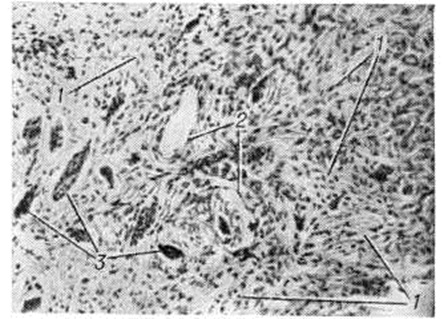

Макроскопически Десмоид представляет собой очень плотный, обычно одиночный узел, на разрезе волокнистого вида, серовато-жёлтого цвета, нерезко отграниченный от окружающих тканей. При микроскопии (рисунок) узел состоит из переплетающихся пучков коллагеновых волокон, не имеющих определённой ориентации, и зрелых фибробластов и фиброцитов. Митозы крайне редки. В периферических отделах Десмоид иногда обнаруживается инфильтрация окружающих тканей элементами новообразования. В зависимости от количества клеток и склонности их к пролиферации выделяют фиброматозный и саркоматозный типы Десмоид Последний близок к фибросаркоме (смотри полный свод знаний), от которой трудно его отличить. В Десмоид возможны очаги ослизнения. Такие опухоли обладают более выраженными инвазивными свойствами и в редких случаях могут давать метастазы.

Рис

Микроскопическая картина десмоидной фибромы: выражены переплетающиеся соединительнотканные волокна (1), мелкие сосуды (2), фибробласты (3).